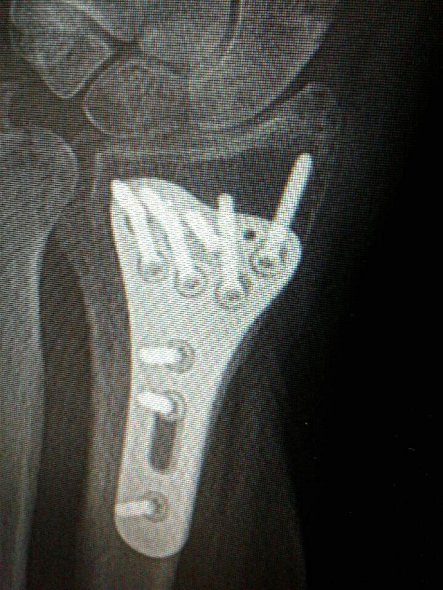

This is a photo snapped with a cellphone of the implant in my wrist, held in place by 10 screws. Minnesota Prairie Roots file photo 2018.

Let’s backtrack. When I slipped on rain-slicked wooden steps in mid-June and fractured my left wrist badly enough to require surgery and implantation of a titanium plate, I heard too many insensitive comments. Topping those was the accusation that my husband pushed me, followed by laughter. I did not hold my words inside. There is absolutely nothing humorous about domestic violence. Nothing. Ever.